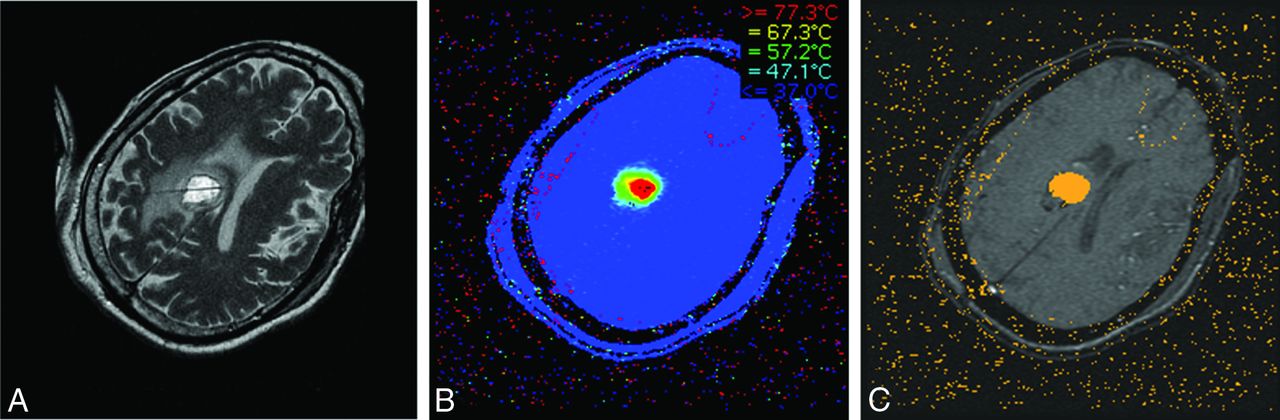

Proton resonance frequency is the most widely used temperature-sensitive MR imaging parameter for real-time MRTI.25 Proton resonance frequency–based MRTI is the basis of MRgLITT. The physical mechanism of proton resonance frequency–based MRTI depends on the presence of hydrogen bonds within a tissue.26⇓–28 As the temperature increases, the number of hydrogen bonds decreases. This decrease leads to a more uniform distribution of electron clouds within a molecule. The more evenly distributed electron clouds are better able to shield the 1H nuclei from the full force of the external magnetic field supplied by the MR imaging machine. Thus, as the temperature increases, the local magnetic field experienced by a 1H nucleus decreases due to increased shielding by the surrounding electrons. The decrease in the local magnetic field decreases the Larmour precession frequency of the 1H nucleus, which, in turn, alters the phase of gradient recalled-echo phase images.25 Measurements are obtained by subtracting “thermal” fast-spoiled gradient recalled phase images (obtained after administration of thermal energy) from a “reference” fast-spoiled gradient recalled phase image (obtained at body temperature before any energy pulse is delivered).26,27 The phase difference, or phase shift, between the 2 images is proportional to the overall temperature change. As such, proton resonance frequency–based MRTI does not measure the absolute temperature of a sample, but simply measures the temperature difference between the sample and a designated reference temperature image.25,28 Temperature information and time of ablation can be incorporated into a mathematic model of thermal tissue destruction (Arrhenius model) to provide a real-time quantitative estimate of tissue necrosis,29 displayed in real-time as an orange “damage zone” (Fig 1).

Once the location of the laser probe is confirmed, ablation can proceed. A, T2 image demonstrates a properly positioned laser probe within a metastatic melanoma lesion. B, Heat map: during ablation, temperatures surrounding the laser tip are continuously updated and depicted with various colors. C, Damage zone images: orange color depicts the area of tissue that has been successfully ablated (damage zone) on the basis of the Arrhenius model of thermal tissue ablation.

Two major LITT platforms are in use today. NeuroBlate (Monteris Medical Corporation, Minneapolis, Minnesota), which received 510(k) FDA clearance in May 2009, uses a 12-W 1064-nm neodymium-doped yttrium aluminium garnet laser with a CO2 cooled side-firing probe.30 Visualase (Medtronic, Minneapolis, Minnesota), which received FDA clearance in 2007, is the platform used in our institution. The major components of the Visualase system include a 15-W 980-nm diode laser, a disposable saline-cooled diffusing laser applicator probe with a 1-cm-long 1.65-mm diameter outer cooling catheter, and a computer workstation, which communicates with MR imaging. MRTI generates “thermal” images, which are then used to generate “damage” images (Fig 1). Treatment concludes when the “damage zone” in a damage image covers the entire target area. The software allows the programming of temperature limit points near the tip of the probe and in the periphery of the lesion. If temperatures exceed the programmed thresholds, the laser shuts down automatically. Recommended temperature limit points are 90°C near the tip of the probe as a safeguard against overheating, carbonization, and vaporization and 50°C at the periphery to prevent damage to adjacent normal brain tissue.31

The procedure can be performed with the patient under light sedation or general anesthesia, depending on patient positioning and preference. The preoperative MR imaging examination identifies the target lesion and entry site. Using intraoperative neuronavigation, we make a small burr-hole by using a twist drill. A bone anchor is then placed into the skull in the exact target trajectory identified by neuronavigation. The cooling catheter is advanced through the anchor to the desired target and fixed to the bone anchor. The laser probe is then inserted into the cooling catheter and locked into place. T2 imaging is performed to confirm the exact placement of the probe (Fig 1A). Fast-spoiled gradient recalled phase images are obtained at the patient's body temperature to serve as a baseline for all intraprocedural thermal measurements. Once the cooling system begins to circulate, a test pulse of 3–4 W for 30–60 seconds is administered to determine the exact location of the distal 1-cm segment of the laser probe. This is important because thermal energy is emitted from the distal-most 1- cm segment of the laser fiber, and knowing its exact location within the target lesion is crucial to ensuring the accuracy of ablation. Ablation is performed by applying treatment doses of 10–15 W for 30–180 seconds until the damage zone covers the entire area of the target lesion. After completion of the procedure, we remove the probe, catheter, and anchor and close the small skin puncture site with a running Monocryl stitch (Ethicon, Cincinnati, Ohio). The reported average hospital stay varies, but most studies report 24–48 hours for cases without complications.29,31⇓–33